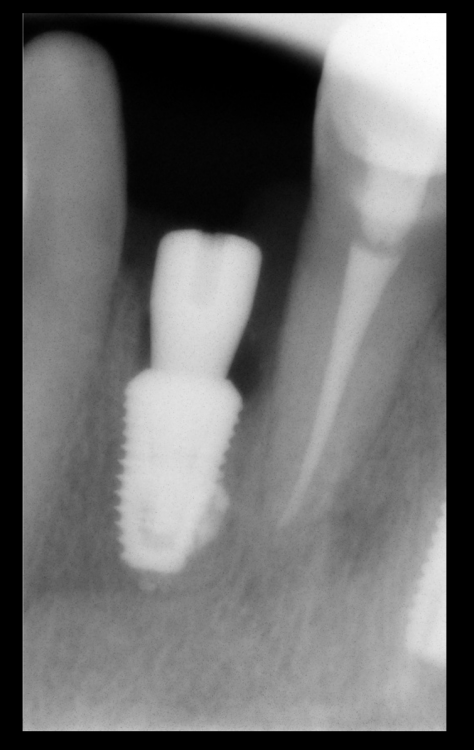

kamranchick Опубликовано 11 декабря, 2021 Поделиться Опубликовано 11 декабря, 2021 сегодня поставил импланатат дентиум, который предназначен для внутреннего рынка в корее, на мой взгляд есть конструктинвые различия в имплантатах небольшие 1 Ссылка на комментарий

Карен Аванесов Опубликовано 22 декабря, 2021 Автор Поделиться Опубликовано 22 декабря, 2021 10.12.2021 в 20:03, kamranchick сказал: Карен приветствую, почему такой толстый имплантатик?:) Торк же?) 07.12.2021 в 22:44, Fin сказал: На втором снимке кажется, что уже есть изменения в периодонте резца. Ключевое слово "кажется", вот и думаю забить. Ссылка на комментарий